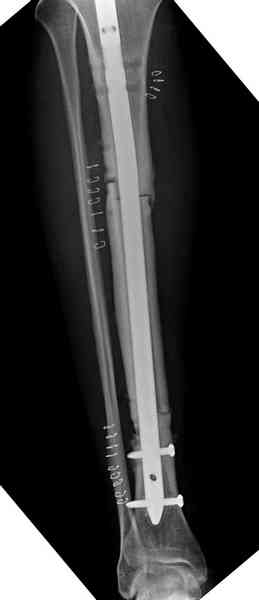

Недавно на нашей ежемесячной Morbidity&Mortality

conference мы разбирали похожий случай, ложный сустав большеберцовой кости после резекции опухоли.

К нашему онкологу-ортопеду обратился больной с жалобами на боли в голени, из рассказа - год назад была сделана биопсия большеберцовой кости, но название заболевания "не запомнил”.

Оперирован в военном госпитале с заменой сегмента

аллокостью большеберцовой кости и после демобилизации явился для постоянного наблюдения по месту жительства.

Наши имели проблему со сращением, пришлось им сделать динамизацию, дополнительную аутопластику.

Снимки представлены.